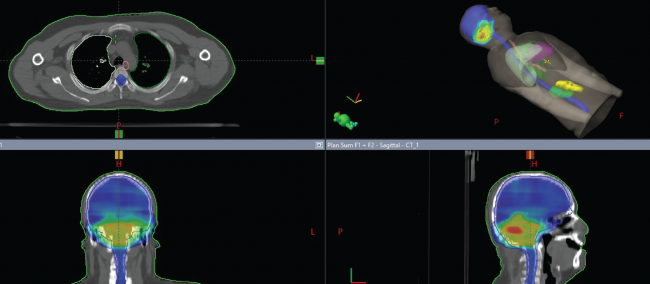

Radioterapia con tecnología adecuada no causa daño permanente, ya que al radiar la laringe el cáncer muere rápidamente y en etapas tempranas de la enfermedad la posibilidad de curase totalmente es por arriba del 95% de los casos.